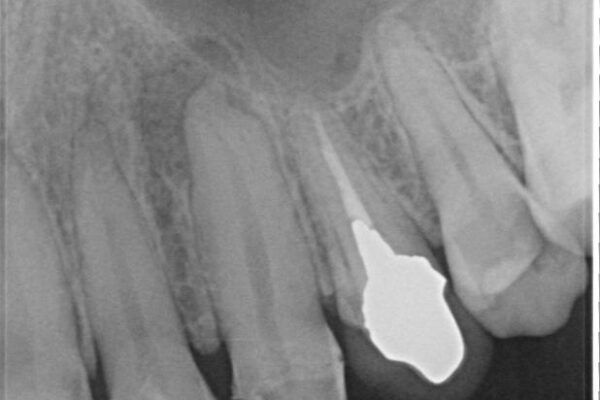

治療途中

• 「抜歯してブリッジ」と言われた20代女性が選んだ治療とは|たった4か月で自然な笑顔に抜歯即時インプラント+審美補綴の症例 治療途中画像